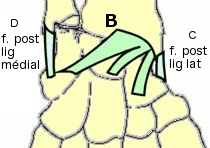

- (A) Le ligament ulno-carpien et radio-carpien palmaire

- (B) Le ligament radio-carpien (old.

- (C) Le ligament collatéral latéral (old.

- (D) Le ligament collatéral médial (old.